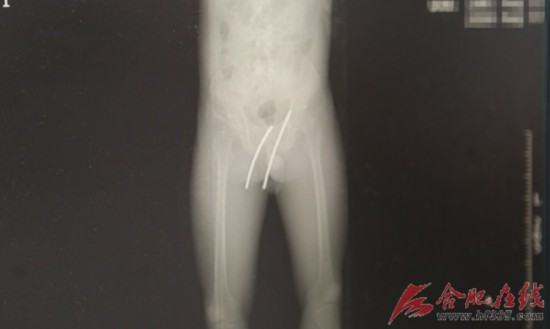

CT显示钢筋所在的位置

通过增强CT显示,这两根钢筋虽然深深的插入了林师傅的身体,但是却避开了体内所有的脏器和血管,实在是不幸中的万幸。该院急诊外科副主任医师卢华东介绍说,只要有一根钢筋稍稍偏离1公分,都有可能伤及直肠或膀胱,就需要做膀胱修复手术或者肠造瘘;从大腿插入的钢筋,只要再偏离3公分,就有可能伤及股动脉,出现失血性休克,甚至导致死亡。